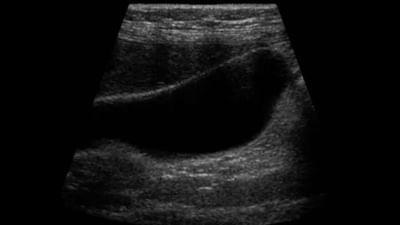

તાજેતરમાં ઓડિશામાં એક ગર્ભવતી મહિલાના ત્રણ અલ્ટ્રાસાઉન્ડ કરવામાં આવ્યા હતા, જે મુજબ ગર્ભનો વિકાસ સામાન્ય રીતે થઈ રહ્યો હતો. પરંતુ રિપોર્ટ અનુસાર, યુએસજીથી વિપરીત, બાળકનો જન્મ અમુક અંગો વગર થયો હતો. સોનોગ્રાફી, જેને ઘણીવાર અલ્ટ્રાસાઉન્ડ તરીકે ઓળખવામાં આવે છે, તે સામાન્ય રીતે જ્યાં માતા-પિતા તેમના બાળકને પ્રથમ વખત જુએ છે. પરંતુ શું તે સલામત છે? અલ્ટ્રાસોનોગ્રામ (યુએસજી) એ એક પરીક્ષણ છે જેમાં વિકાસશીલ બાળક અને માતાના પ્રજનન અંગોની તસવીર બનાવવા માટે હાઇ ફ્રિકવન્સી સાઉન્ડ વેવ (ઉચ્ચ આવૃતિ ધ્વનિ તંરગો) નો ઉપયોગ કરવામાં આવે છે.

ડૉ. દેવરુખકરના જણાવ્યા મુજબ, ગર્ભાવસ્થા દરમિયાન લગભગ 5 થી 7 અલ્ટ્રાસાઉન્ડ પૂરતા ગણવામાં આવે છે, સિવાય કે પ્રથમ ત્રિમાસિકમાં રક્તસ્રાવ અથવા સ્પોટિંગના કોઈ સંકેતો ન હોય. નિષ્ણાતોના મતે, પ્રથમ ત્રિમાસિકમાં અલ્ટ્રાસાઉન્ડ ડાઉન સિન્ડ્રોમ ગર્ભની તપાસ કરવા માટે કરવામાં આવે છે કે હૃદયના ધબકારા છે કે નહીં. બીજું સામાન્ય રીતે ડાઉન સિન્ડ્રોમ માટે 11 થી 13 અઠવાડિયાની વચ્ચે કરવામાં આવે છે અને નુચલ અર્ધપારદર્શકતા ચકાસવા માટે – નુચલ અર્ધપારદર્શકતા એ બાળકની ગરદનની ચામડી નીચે એકત્ર કરવામાં આવતું પ્રવાહી છે.

ત્રીજો 18 થી 20 અઠવાડિયાની વચ્ચે કરવામાં આવે છે તે તપાસવા માટે કે શરીરના તમામ અંગો યોગ્ય રીતે વિકસિત થયા છે કે નહીં. ડૉ. દેવરુખકરે એમ કહીને સમાપન કર્યું કે અલ્ટ્રાસાઉન્ડ સિવાય, એમઆરઆઈને પણ ગર્ભાવસ્થા દરમિયાન સલામત વિકલ્પ માનવામાં આવે છે. જો કે એમઆરઆઈ અને સીટી સ્કેનમાં રેડિયેશન હોવાનું કહેવાય છે.